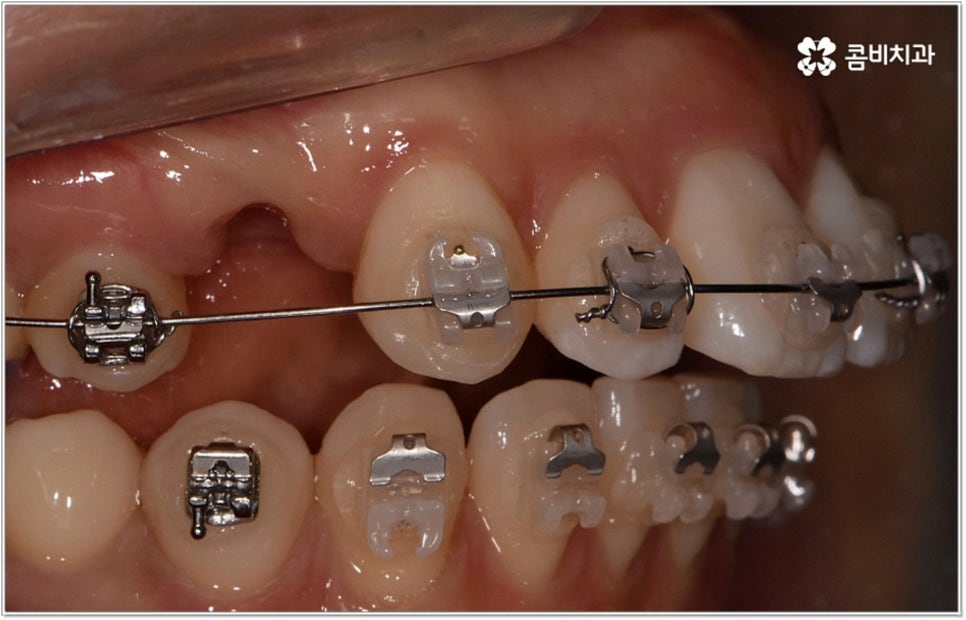

청소년기는 교우 관계에 영향을 많이 받고 외모에 민감할 때라 교정기에 대한 반감이 있을 수 있으나 바로 이때가 치아 이동에 있어 매우 중요한 시기이므로 제대로 이해할 수 있도록 차근차근 설명해 줄 필요가 있는데요. 12~15세 사이, 즉 초등학교 고학년에서 중학교 저학년 사이가 유치에서 영구치로 거의 다 교체되고 잇몸뼈가 계속해서 성장하는 나이이기 때문에 상악과 하악의 균형잡힌 발달을 유도하면서 부정교합을 바로잡고 치열을 가지런하게 만드는데 보다 빠르고 효율적인 만큼 가능하다면 이 시기를 놓치지 않는게 중요한 거예요. 물론 성인분들도 상황에 맞게 교정 치료를 진행할 수 있지만 부정교합의 종류와 정도에 따라 성장기 교정 치료를 진행하는 것이 좀 더 나은 케이스가 있으니 아이의 치열에 관심을 가지고 정확하게 알아보시는 것이 도움이 될 수 있습니다.

무리하지 않고 돌출입치아교정 과정을 진행하기 위해서는 먼저 꼼꼼한 검진 및 분석에 따른 철저한 맞춤 치료 계획 수립이 중요하다고 할 수 있는데요. 특히 3D CT 및 모르페우스 시스템을 통해 현재 아이의 치열이나 연조직, 상하악 관계 등을 자세히 살펴보고 안모 분석 후 교정 치료가 끝난 예상 모습을 시뮬레이션해서 보여주면 환아의 흥미를 유발하고 앞으로 진행될 사항에 대한 이해도를 높여줄 수 있어 긍정적인 영향을 줄 수 있으니 정밀 검진 장비를 갖추고 숙련된 의료진이 치료하는 치과에서 돌출입치아교정 과정을 진행하시길 권유드리고 있어요.